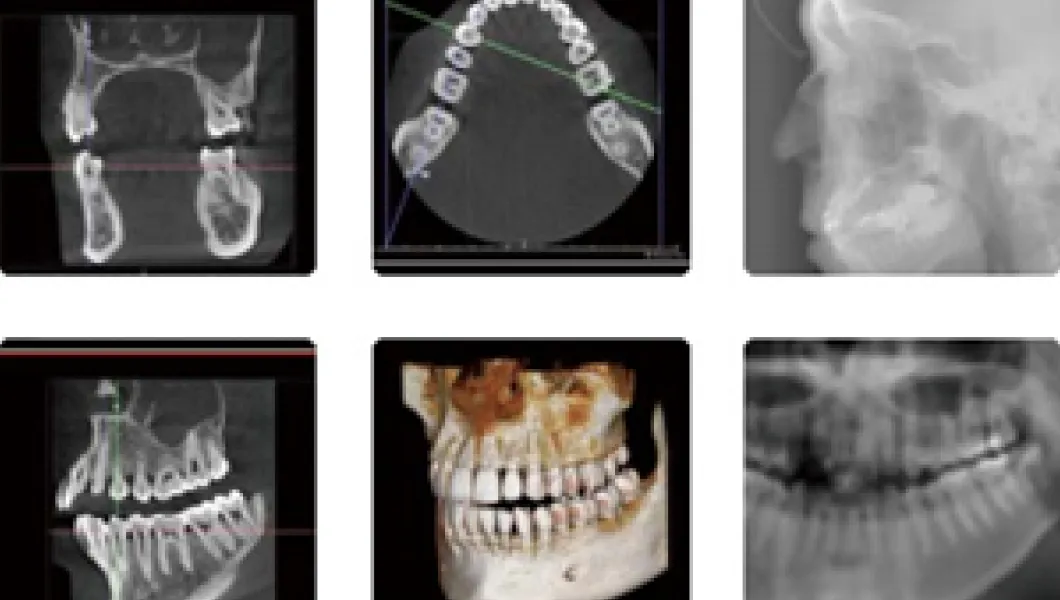

世界最高峰のX線CT診断装置Fine Cube E2を導入

今までの一般的なレントゲンで見ていたものは平面的な画像でしかありませんでした。

虫歯や歯周病、顎関節の病態をおおまかに捉えることは可能ですが、あくまでも影絵なので、骨の幅や形などを見ることは絶対にできません。

対してCTは立体的にこれをとらえることができるため歯科医師はさらに詳細に診断を行えますし、説明を受けられる患者さんにもご自身の現状をわかりやすく伝えることができます。